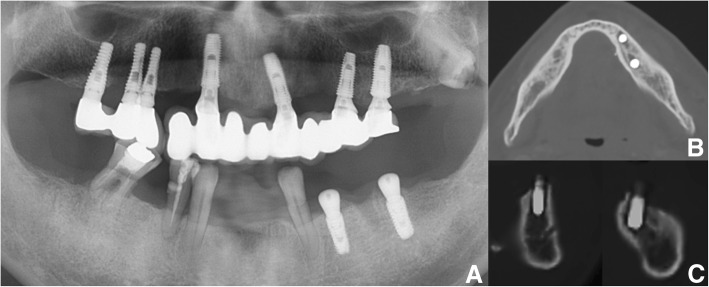

Most reports on oral bleeding associated with ITP describe preoperative management and management of spontaneous gingival oozing and bruising as oral symptoms of ITP [8, 10]. Furthermore, only two reports have described bleeding after surgery or procedures in patients with ITP [1, 11] (Table 2), and these studies did not cover life-threatening massive bleeding after tooth extraction or dento-alveolar fracture, as in the present report. In addition, most published studies on severe postoperative hemorrhage after dental implant surgery mention that the majority of life-threatening hemorrhages result from inadequate surgical skill and damage to an anatomical structure, such as rupture of the lingual artery or mandibular lingual cortex perforation, which typically occurs in the anterior region including the premolars between the mental foramens [12–14] (Fig. 4). The dental implant in this case report was placed in the posterior mandibular area, which had no atrophic status, and no anatomic structural damage or lingual cortex perforation had occurred.

Fig. 4.

a Panoramic view: dental implant installation state on mandible Lt. Posterior area (bleeding area). b Axial CT view and c sagittal CT view on implant site showed adequate placement of dental implant without lingual cortex perforation and damage of adjacent anatomic structure. The dental implant installation in the left posterior mandibular area